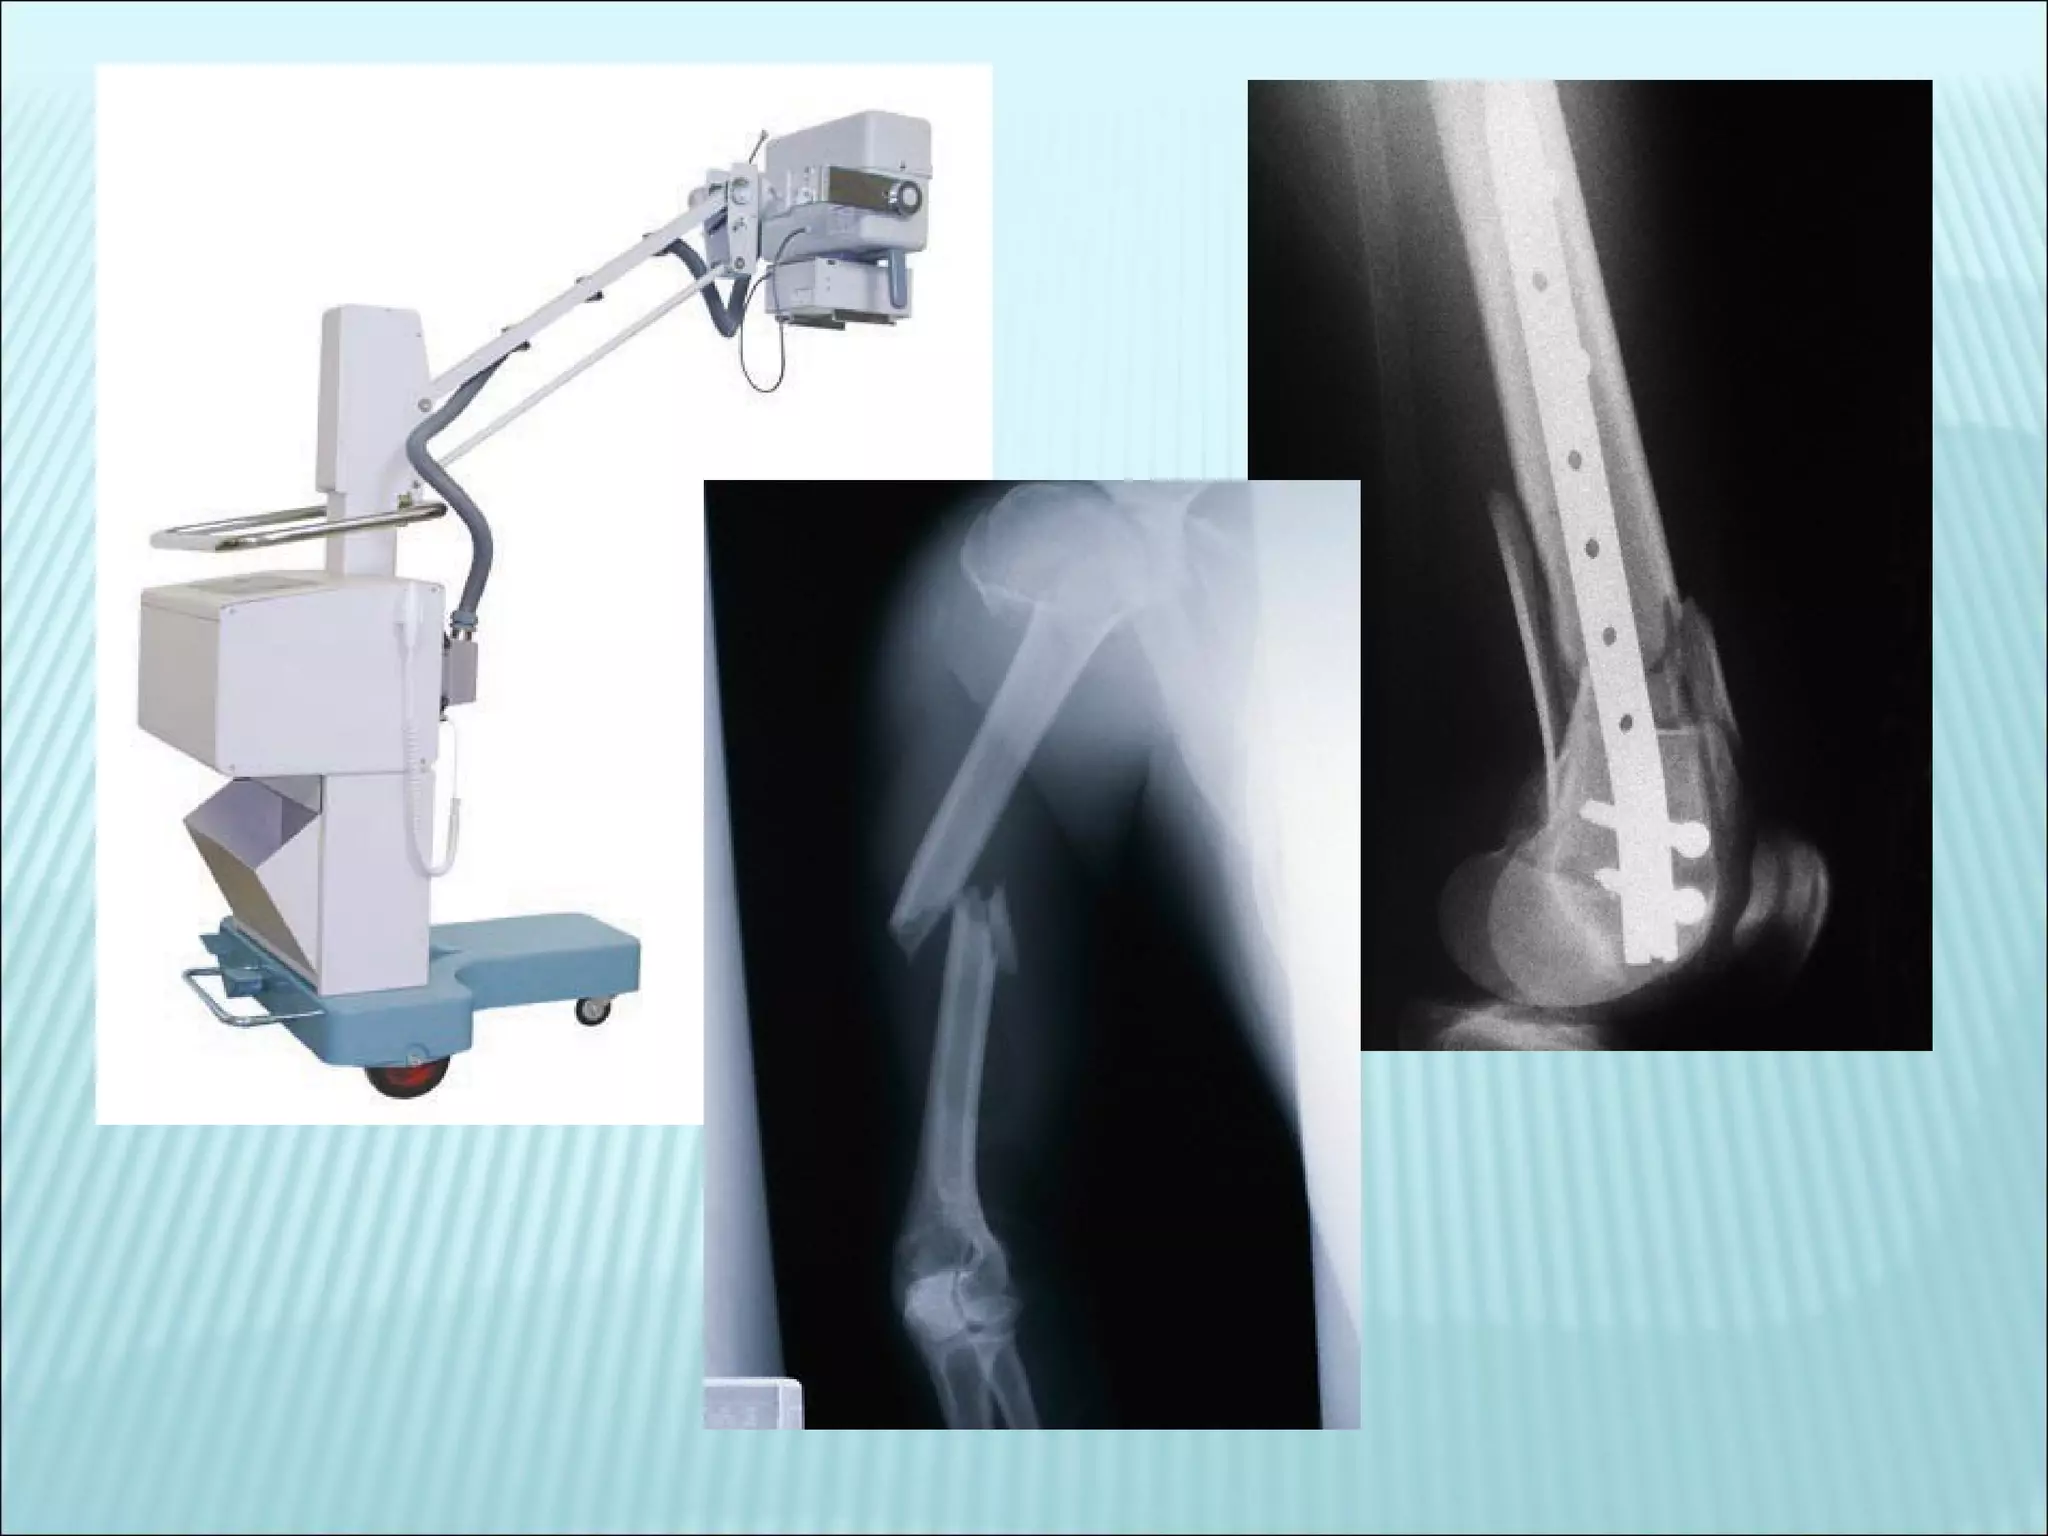

Even  shorter wavelengths  with  higher frequencies  are the X-rays.  These waves  pass through tissue  (skin and muscle) and are  absorbed by the bones .  This radiation always  stays in the bone  and builds up over time.  People who work as technicians taking the x-rays must protect themselves, by leaving the room where the x-ray is taken and also protect the patient's other areas of the body with lead vests to prevent over-exposure.

Even shorterwavelengths with higher frequencies are the X-rays. These waves pass through tissue (skin and muscle) and are absorbed by the bones . This radiation always stays in the bone and builds up over time. People who work as technicians taking the x-rays must protect themselves, by leaving the room where the x-ray is taken and also protect the patient's other areas of the body with lead vests to prevent over-exposure.